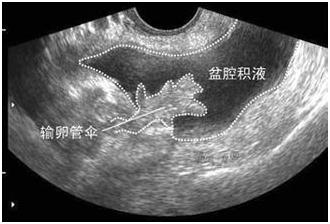

受精卵在子宫体腔以外着床的现象称为异位妊娠,最常见的是输卵管妊娠。当输卵管妊娠流产或破裂,就会输卵管壁破裂出血,血液聚积在子宫直肠陷凹,进而形成盆腔积液。从后穹窿能够抽吸出不凝固血液。